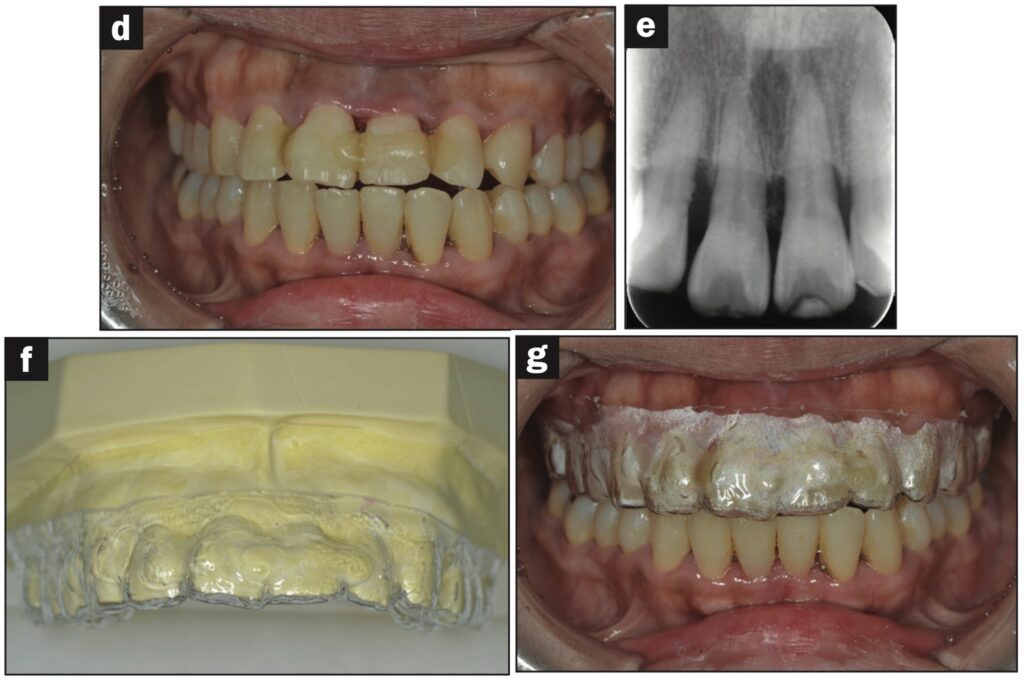

Bệnh nhân nữ 42 tuổi bị ngã khiến răng cửa giữa hàm trên bên trái bị lệch về phía vòm miệng. Đường gãy xương ổ răng ở phía khẩu cái được thấy trên CBCT.

Răng được nắn chỉnh và cố định bằng composite quang trùng hợp rồi lấy dấu. Hai tiếng sau, bệnh nhân quay lại và nhận khay duy trì. Bệnh nhân được hướng dẫn đeo khay duy trì cả ngày trừ khi đánh răng.

Các thử nghiệm tủy được thực hiện sau 7 và 28 ngày. Đánh giá độ lung lay răng, gõ và sờ, thử tủy EPT và chụp X quang được thực hiện sau 28 ngày.

Sau 28 ngày theo dõi, răng hơi lung lay và không đáp ứng với thử tủy EPT. Sau 2 tháng theo dõi, răng không bị đổi màu, không lung lay, âm tính với EPT và hơi nhạy cảm khi gõ. Không có tổn thương quanh chóp trên X quang và không có lỗ dò. Sau 3 tháng theo dõi, răng đã đáp ứng với EPT (9/10) và có cảm giác đau nhẹ khi gõ.

Sau 4 tháng theo dõi, răng đã phản ứng với EPT (9/10) và không còn nhạy cảm với gõ.